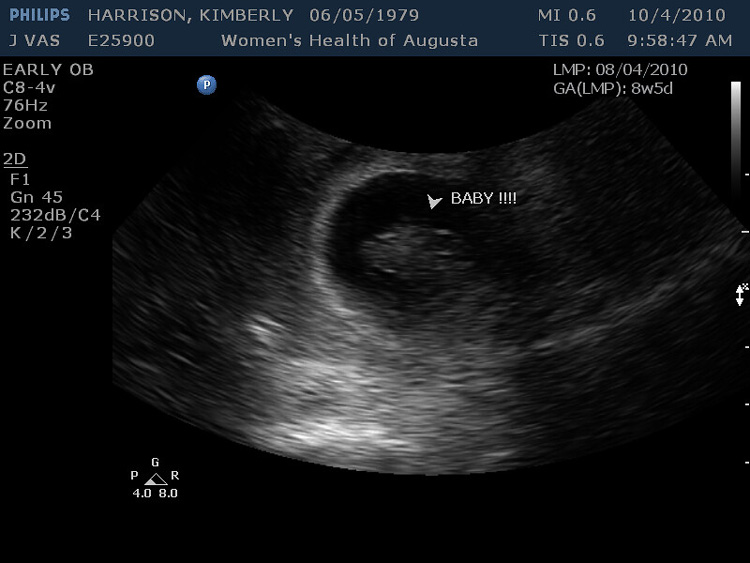

Getting Texted a Sonogram

I was in a five-year relationship with my girlfriend when this happened. I started talking to an old colleague from when I was a teen. I always had the hots for her, but because we lived in different states, I knew nothing would come of it. But then I learned that she had family in my city who she visited regularly….

We decided to meet up for dinner just to catch up, but we ended up getting drunk, booking a hotel room, and making good use of it. It became a regular thing over the next few months until she texts me a sonogram of our child. I planned on telling my girlfriend the truth because I didn’t have a father growing up, and I’d never want my child to experience that.

However, she lost the baby a month into the pregnancy, and that was the end of our relationship. I’ve never felt so guilty and anxious. I would never do it again. Reddit User: [redacted]